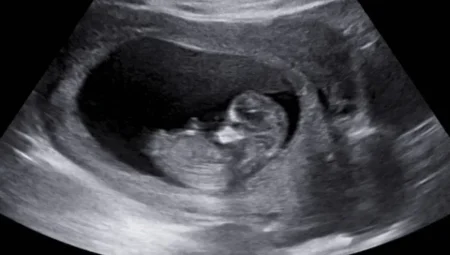

Tarihte Bir İlk: SMA’lı Çocuk, Anne Karnında Tedavi Edildi!

ABD’deki bilim insanları, tarih yazacak bir başarıya imza attı. Spinal Müsküler Atrofi (SMA) hastalığına sahip…